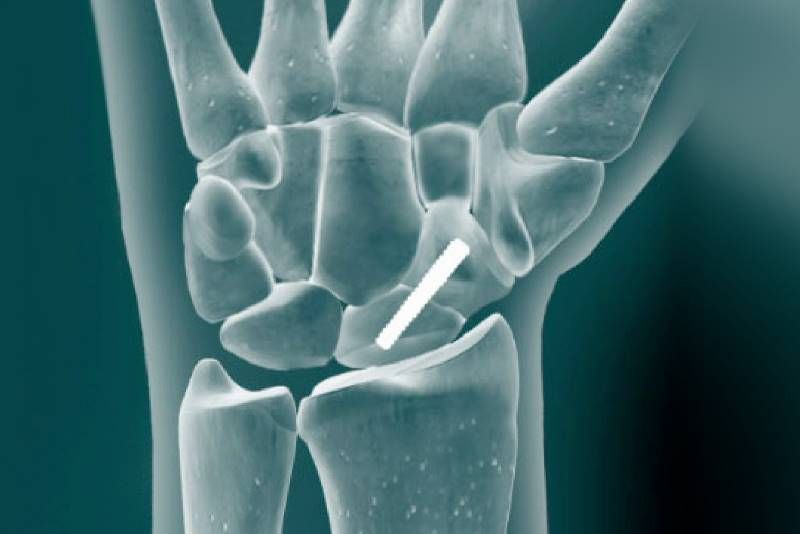

Ανοικτή ανάταξη και εσωτερική οστεοσύνθεση (με πλάκα και βίδες)

Με τη χειρουργική αυτή μέθοδο, τα οστικά τμήματα αρχικά ανατάσσονται (δηλαδή επανατοποθετούνται) στην ανατομική τους θέση. Ακολουθεί η συγκράτηση του οστού σε αποδεκτή θέση με ειδικά εργαλεία ανάταξης και η τελική θέση συγκράτησης επιτυγχάνεται με χρήση ειδικών πλακών οι οποίες προσαρμοζόνται με βίδες επάνω στο οστό.

Ανατάσσουμε ανοικτά (με χειρουργική τομή) το κάταγμα και στη συνέχεια το συγκρατούμε με χρήση υλικών οστεοσύνθεσης (πλάκα και βίδες) επάνω στο σημείο που έσπασε το κόκκαλο. Υπάρχουν συγκεκριμένοι κανόνες αυτής της διαδικασίας. Το πλεονέκτημα είναι, ότι μπορούμε να επιτύχουμε υπό άμεση όραση την ανάταξη του κατάγματος (επαναφορά του οστού στην φυσιολογική του θέση). Αυτό βοηθάει σημαντικά την επιτυχημένη πώρωση του οστού (να κολλήσει δηλαδή σωστά και γρήγορα).